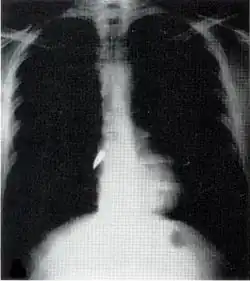

La mayoría de las lesiones son heridas en el tórax y tienen una tasa de mortalidad de menos del 10 %.[11] El traumatismo torácico penetrante puede dañar órganos vitales como el corazón y los pulmones y puede interferir con la respiración y la circulación. Las lesiones pulmonares que pueden ser causadas por un traumatismo penetrante incluyen laceración pulmonar (corte o desgarro), contusión pulmonar (moretón), hemotórax (una acumulación de sangre en la cavidad torácica fuera del pulmón), neumotórax (una acumulación de aire en la cavidad torácica) y hemoneumotórax (acumulación de sangre y aire). La succión del traumatismo torácico y la tensión del neumotórax puede resultar.

El traumatismo penetrante también puede causar lesiones al corazón y al sistema circulatorio. Cuando el corazón es perforado, puede sangrar profusamente en la cavidad toráxica si la membrana que lo rodea (el pericardio) se desgarra significativamente, o puede causar taponamiento cardiaco si el pericardio no es interrumpido.[12] Las fracturas de costillas comúnmente producen traumatismo de tórax penetrante cuando los huesos afilados atraviesan los tejidos.